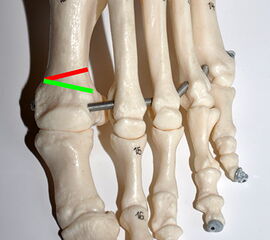

Abbildung 1

• Korrekturpotential größer als beim offenen Chevron, da die Gelenkkapsel als stabilisierendes Element erhalten bleibt und über eine trikortikale Osteosynthese mit zwei kanülierten Schrauben eine Verschiebung bis ca. 80% des Metatarsaledurchmessers möglich ist (Abb. 1).